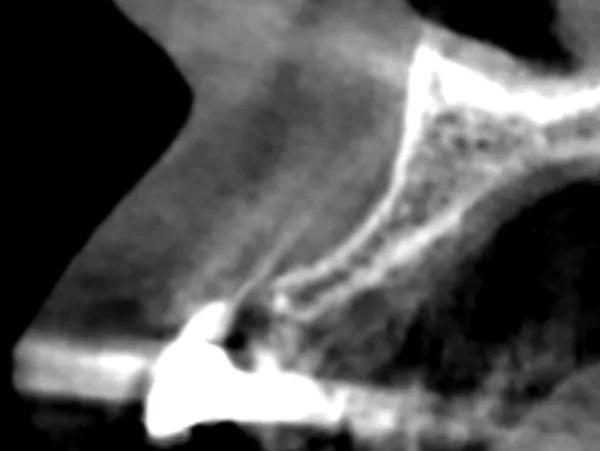

Женщина, 63 года, с неотягощенным анамнезом, явилась для восстановления левого квадранта нижней челюсти; в нем отсутствовали левые первый и второй моляр, а также были поражены второй премоляр и третий моляр, причем последний был наклонен мезиально из-за преждевременной потери второго моляра (Фото 2 и Фото 3). Было запланировано удаление разрушенных зубов с одновременным восстановлением гребня на участке дефекта от второго моляра до первого премоляра с помощью костного трансплантата и рассасывающейся коллагеновой мембраны.

Фото 3: КЛКТ перед операцией, левый первый моляр нижней челюсти.